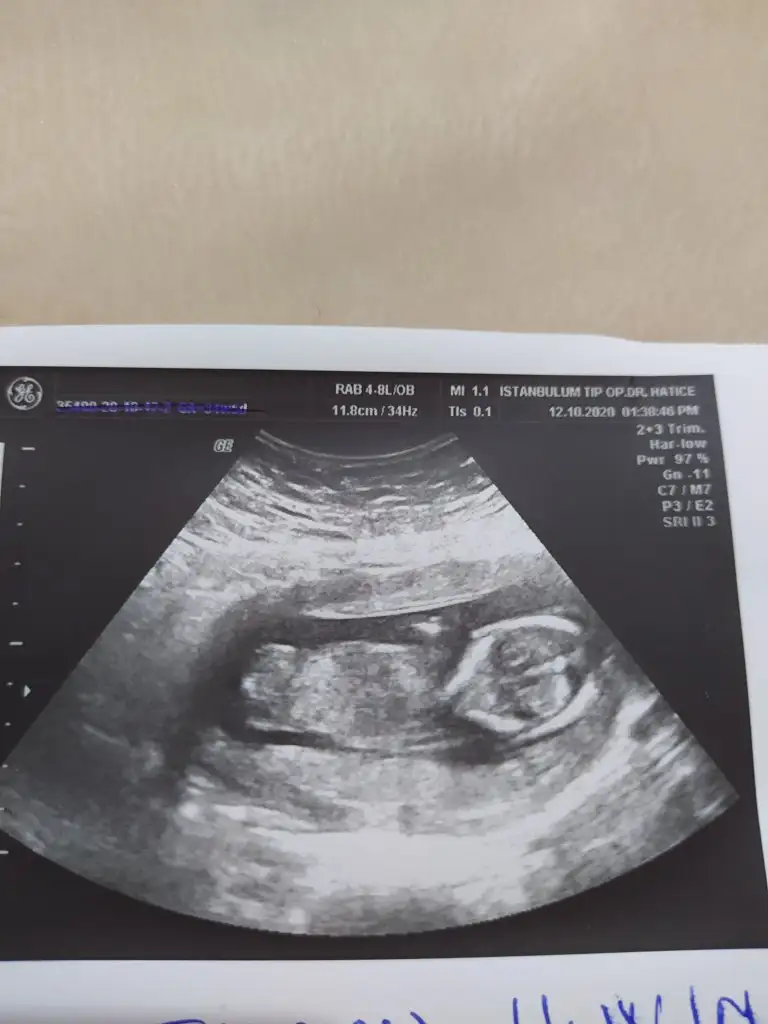

Erkek gibi gibiTahmın alabılır mıyım bende kuzenımın usg fotosu

E bu benimkiyle aynıIkra meyra cığım benim diğer görüntüme kız dedin. Bi de bu açıyı göndereyim bu ne olabilir

Ya bana da kız gibi geliyor bizimki. Sizin doktor tahminde bulundu mu?Ay dünden beri bakıyorum bakıyorum anlayamadım,açıkça anlayamıyorsak zaten kızdır kesin30 ekimde net öğrenicez o zaman anketini de oylayacağım büyük ihtimalle kız evet, benim canım kızım